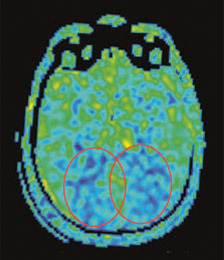

messung_hirndurchblutung

Abb. 2a

Messbild der Hirndurchblutung eines Patienten mit Farbkarte der Durchblutungsmessungen. Die Durchblutungsminderungen sind zum Hinterhaupt (okzipital) betont (innerhalb der Ovale), somit ebenfalls untypisch für eine Alzheimer-Erkrankung. Hier kommt eine andere Demenzform, z. B. die sogenannte Lewy-Körper-Demenz (LBD), in Betracht.

Moderne MRI-Techniken erlauben die Messung der Hirndurchblutung in verschiedenen Arealen, auch ohne intravenöse Kontrastmittelgabe. Die Durchblutungsminderungen betreffen je nach Erkrankung unterschiedliche Hirnareale, gehen dem Gewebeschwund in der Regel weit voraus und können wiederum anhand des Verteilungsmusters auch im Frühstadium wichtige Hinweise auf die Art der neurodegenerativen Erkrankung liefern (Abb. 2b). Bei der Alzheimer-Erkrankung z. B. stehen Durchblutungsminderungen in den Schläfen- und Scheitellappen im Vordergrund.